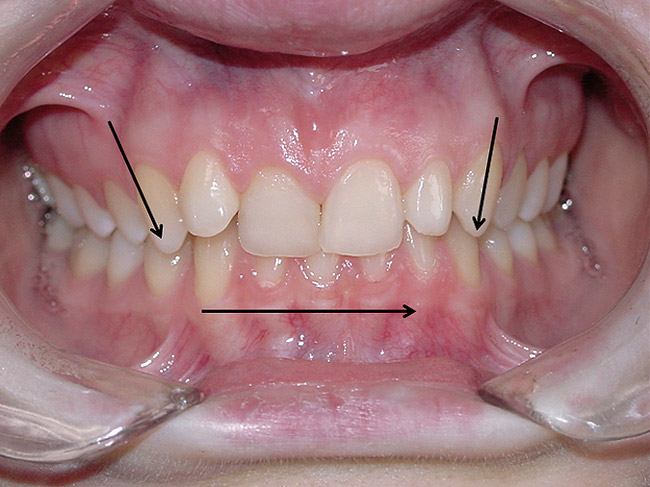

The position, shape, length, and inclination of the maxillary canines will affect the anterior frenal midline position of the mandible. This position may or may not coincide with the midline of the teeth, but gives an indication of the location of the left and right condyles in their fossae. The canines serve as lateral positioners of the mandible. The more lingual the maxillary canine inclination on one side, the more the mandible will shift to the opposite side and the condyle distalize on the opposite side (Figure 6, Figure 7 and Figure 8).

Figure 6  The inclination of the canines provide  the midline position of the mandible. When these  teeth are inclined (eg, the right canine in this  case), they tend to shift the mandible away from  the midline (in this case toward the left).

Figure 7  The left side of the patient shows how  maxillary molars and premolars can cause the  mandibular molars to be lingually inclined as  the teeth come into occlusion.

Figure 8  This case shows the shift of the  mandible from the point of first contact to full  closure because of the anterior restriction, which  has caused the mandible to shift posteriorly and  to the left. This patient experienced symptoms  of right lateral pterygoid tenderness with left  TMJ pain, left-sided headaches, and neck stiffness.  Release of this restriction allowed the  mandible to reposition itself to the midline with  reduction of the symptoms.